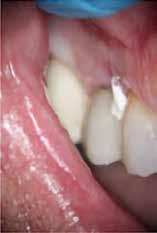

ai felvételek segítségével viszonylag jól el lehet különíteni a külső rezopció okozta ártalmaktól. A belső rezorpciótól szenvedő fogak esetében a radiológiai felvételek excentrikus irányból történő elkészítése során a rezorptív lézió a fog gyökércsatornájával egy irányba mozdul el a felvételen, míg külső rezorpció esetében le fog vetülni a gyökércsatornáról. 1999 márciusában egy 47 éves hölgy páciens arcduzzanattal kereste fel a rendelőnket. Klinikai vizsgálat során a jobb felső nagymetszőfog (11) kopogtatásra való érzékenységét tapasztaltuk. A felső front régióról készült periapikális felvételeken a frontfogakban lévő nagy kiterjedésű III. és IV. osztályú restaurátumokat észleltünk. Az 11-es fog gyökércsúcsa körül periapikális felritkulás volt látható. A 21-es fognál a gyökér középső harmadában belső rezorpciót észleltünk (13. ábra). A páciens kérdésünkre elmondta, hogy a bal felső nagymetszője közel 35 évvel ezelőtt traumás sérülést szenvedett. Mivel abban az időben CBCT-felvételek készítése nem volt számunkra elérhető, így a klinikai adatok alapján azt feltételeztük, hogy a rezorptív lézió bukkális irányba perforálta a gyökércsatorna falát, majd ezt követően az ezt a területet fedő bukkális csontállományt is destruálta.

13. ábra: A periapikális felvételen jól lekövethető a 11-es fog gyökércsúcsa körül látható radiolucens terület körvonala. A 21-es fog gyökerének középső harmadában pedig belső rezorpció jelenlétére utaló jelek észlelhetőek. A rezorptív lézió frontális és laterális irányban is áttörte a csontos falakat, amely következtében a gyökeret körülvevő csontállomány is károsodott. – 14. ábra: A posztoperatív felvételen jól megfigyelhető a 11-es fogba helyezett gyökértömés. A 21-es fog ellátása során a gyökércsatorna megmunkálását csak a rezorptív defektus koronális határáig végeztük. A gyökércsatorna zárására fehér MTA-t alkalmaztunk. – 15. ábra: A 11-es fog gyökércsúcsa körül látható felritkulás teljesen eltűnt. A rezorptív defektus mérete csökkent, valamint a rezorpciós üreg csontosodására utaló jelek is megfigyelhetőek. – 16. ábra: A saggitalis irányú CBCT-metszeten jól látható, hogy a 21-es fogat ép és jól megtartott bukkális kortikális csont fedi. A rezorpciós üreg mérete jelentősen csökkent, valamint az üreg kalcifikálódott anyaggal való telődése is megfigyelhető volt.